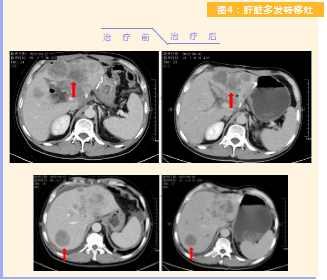

患者完成1周期治療后,上腹部疼痛癥狀基本消失,梗阻性黃疸癥狀緩解,腫瘤指標下降(圖1),肺部多發(fā)轉移灶消失和縮?。▓D2),雙肺門淋巴結縮?。▓D3),肝臟多發(fā)轉移灶縮?。▓D4)。